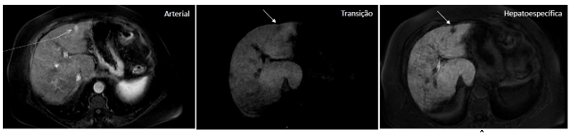

<content:encoded><![CDATA[<p>Rutinariamente, en la resonancia magnética (RM) del abdomen, se utiliza el contraste extracelular inespecífico (gadolinio), que se distribuye de acuerdo con la distribución de los vasos y capilares sanguíneos y determina, así, un patrón dinámico de impregnación de la lesión focal hepática en las fases arterial, portal (venosa) y equilibrio.</p>

<p>En casos seleccionados, se pueden indicar los contrastes intracelulares específicos, también denominados de hepato-específicos y que pueden ser de dos clases principales: (1) óxido de hierro superparamagnético y (2) hepatobiliares, siendo este último captado específicamente por las células hepáticas y con excreción renal (50%) y biliar (50%). En Brasil, está aprobado el contraste hepatobiliar, conocido como ácido gadoxético (Gd-EOB-DTPA, PrimovistÒ).</p>

<p>De esta manera, además de proporcionar los datos habituales del estudio dinámico, existe la etapa final de evaluación hepatobiliar, después de aproximadamente 10 a 20 minutos de la inyección endovenosa, en la cual el contraste entra en los hepatocitos a través de los transportadores de membrana (OATP1, B1/B3) y sale a través de proteínas dependientes de ATP resistentes a múltiples fármacos (MRP2, MRP3, MRP4), siendo el transportador MRP2 el encargado de excretar el contraste en el canalículo biliar.</p>

<h2 class="wp-block-heading"><strong>¿Cuáles son las indicaciones del contraste hepatobiliar?</strong></h2>

<p>Sabiendo que el ácido gadoxético es captado por los hepatocitos y excretado en aproximadamente un 50% por la vía biliar, se espera que un tejido hepático normofuncionante sea impregnado por el contraste en la fase hepatobiliar. De esta manera, la no captación del ácido gadoxético en la fase hepatobiliar infiere que no hay hepatocitos o canalículos biliares viables en la lesión evaluada.</p>

<p>Podemos enumerar 3 indicaciones principales en el uso del ácido gadoxético en la evaluación de lesiones focales hepáticas:</p>

<h3 class="wp-block-heading">1. <strong>Diferenciación entre hiperplasia nodular focal (HNF) y adenoma</strong></h3>

<p>El adenoma y la HNF son el tercer y segundo tumores hepáticos benignos más frecuentes, respectivamente.</p>

<p>El adenoma se caracteriza por cordones de hepatocitos y ausencia de conductos biliares o tractos portales, por lo tanto, no presenta captación en la fase hepatobiliar.</p>